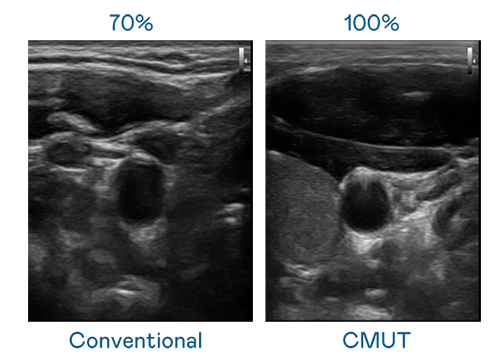

CMUT 技術是一種用電容式微機電元件來產生超音波訊號的技術。與傳統 PZT 壓電式技術相比,CMUT 頻寬增加 30%,更寬頻的超音波訊號讓影像解析度大幅提升,是實現高影像品質醫療超音波掃描、促進精準醫療發展的關鍵技術。

超音波影像的解析度高低,首先取決於探頭能發出的訊號頻寬。ibet CMUT 可提供高清晰的超音波訊號,提供高頻寬、高靈敏度、影像紋理細節更高的超音波影像,協助醫護人員縮短影像判讀時間及利用精準的醫療影像進行診斷。